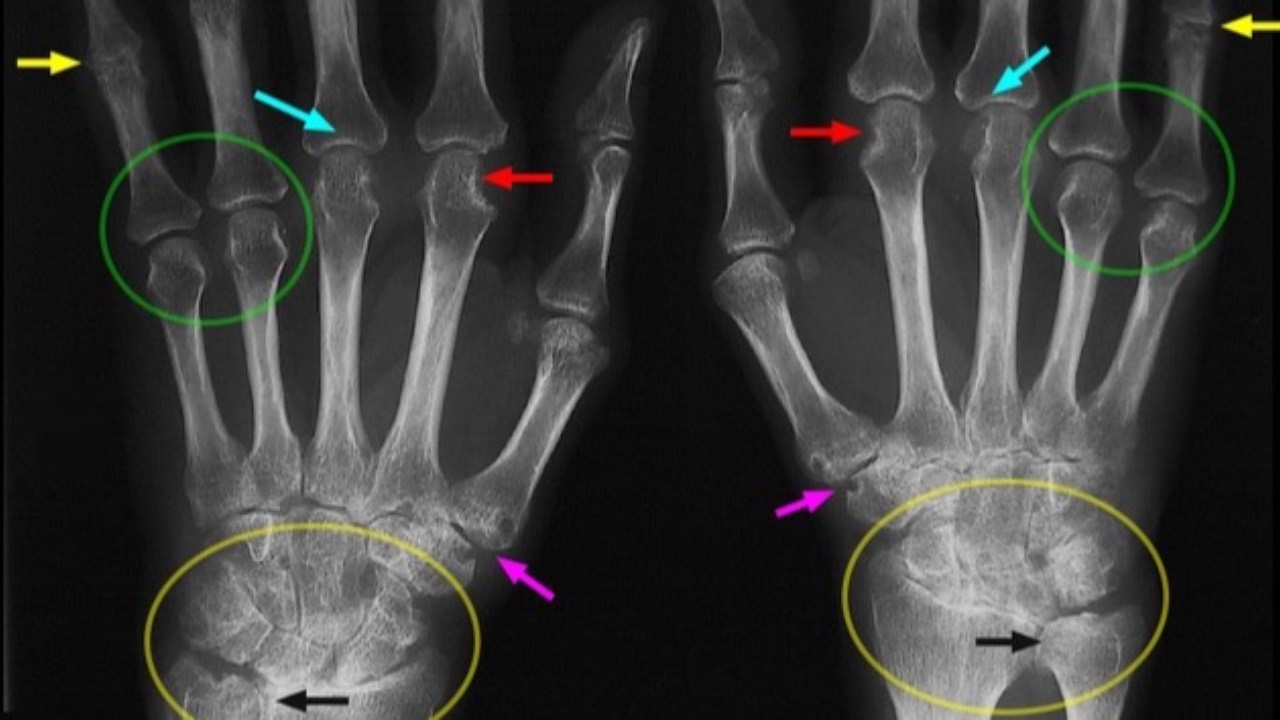

Macular Degeneration & Rheumatoid Arthritis

Is there a connection?

An article published recently in Nature found potential immnunopathologic links between age-related macular degeneration (AMD) and rheumatoid arthritis (RA). A large-scale nationwide cohort study in South Korea found individuals with AMD had an 11% higher risk of developing...